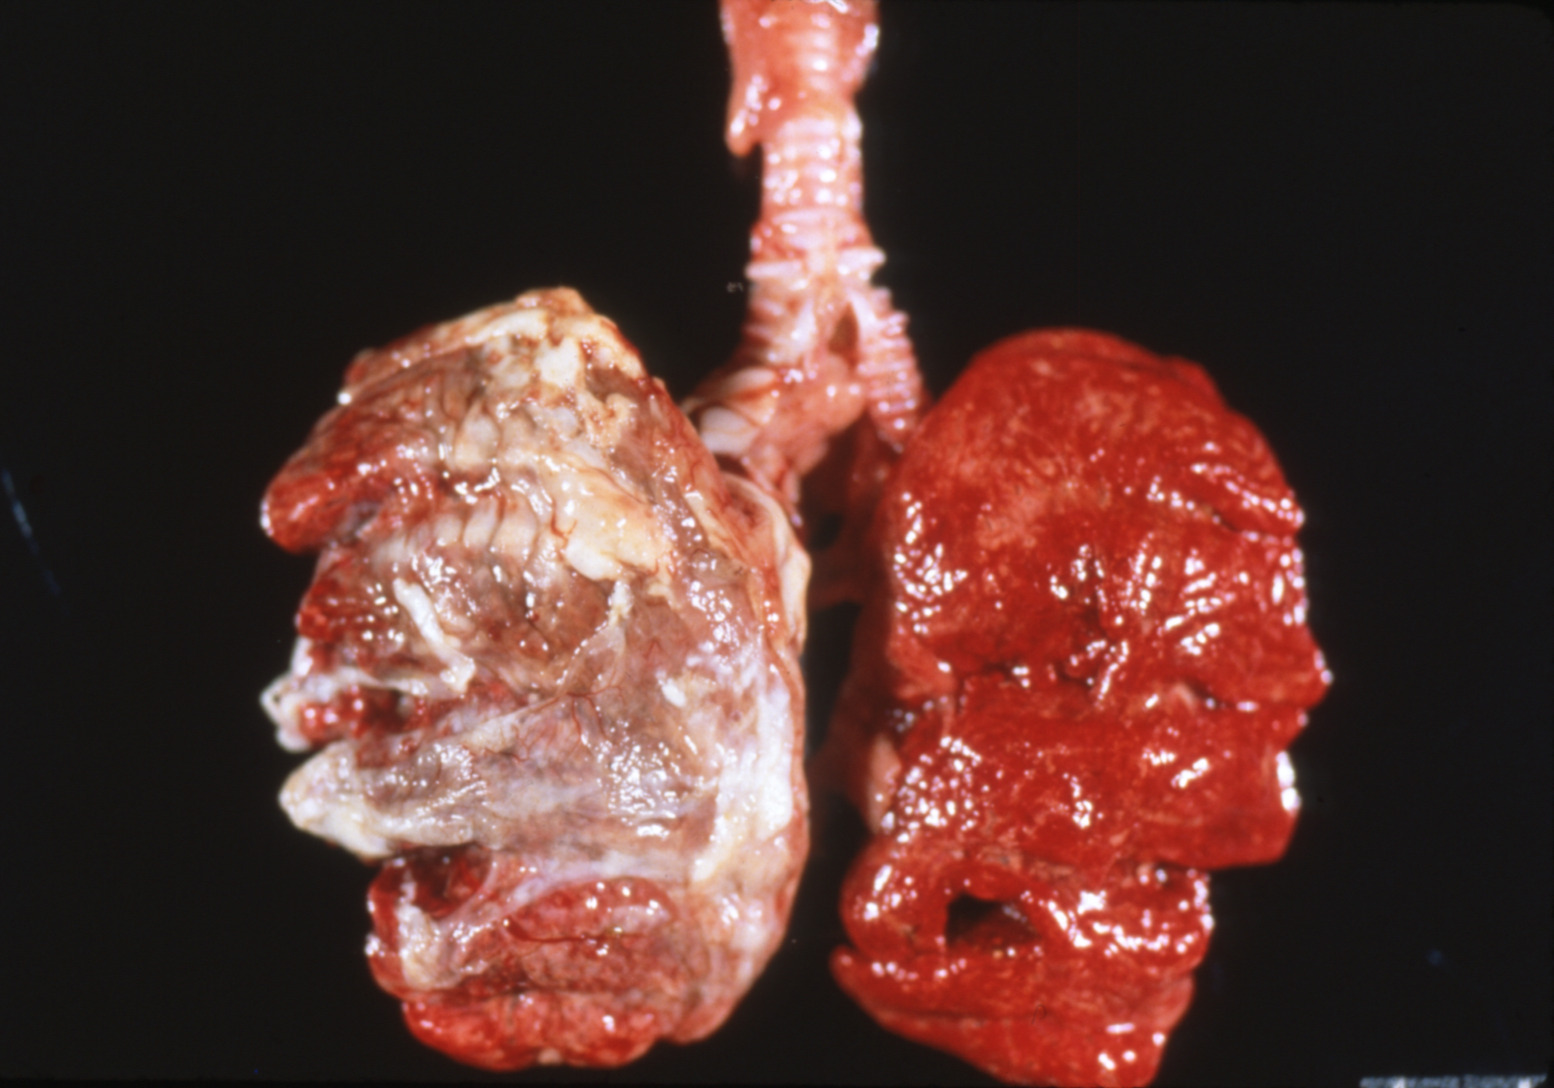

Fowl cholera (slide study set no. 19) Item Info

Fowl cholera (slide study set no. 19)

Poultry--Diseases Chicken cholera